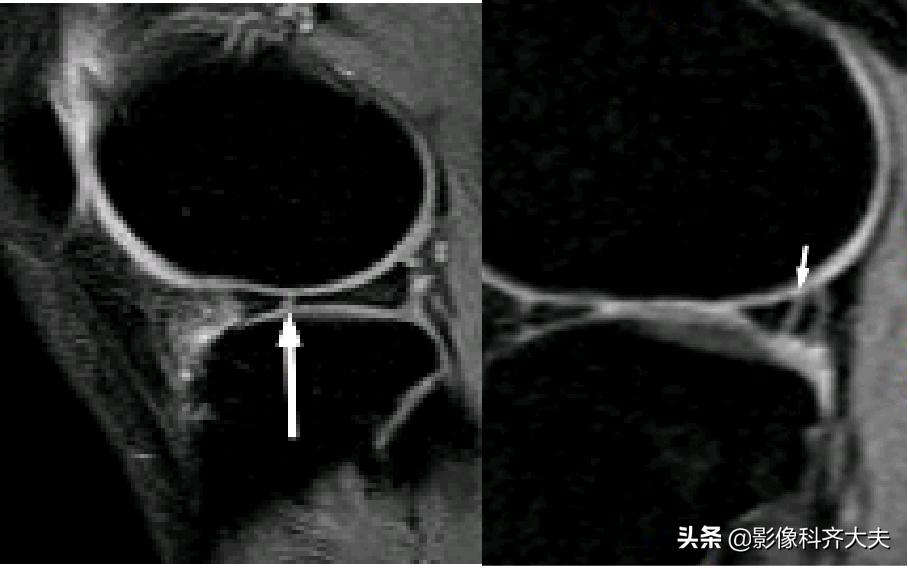

关节内气体伪影:

内侧半月板后角上隐窝: